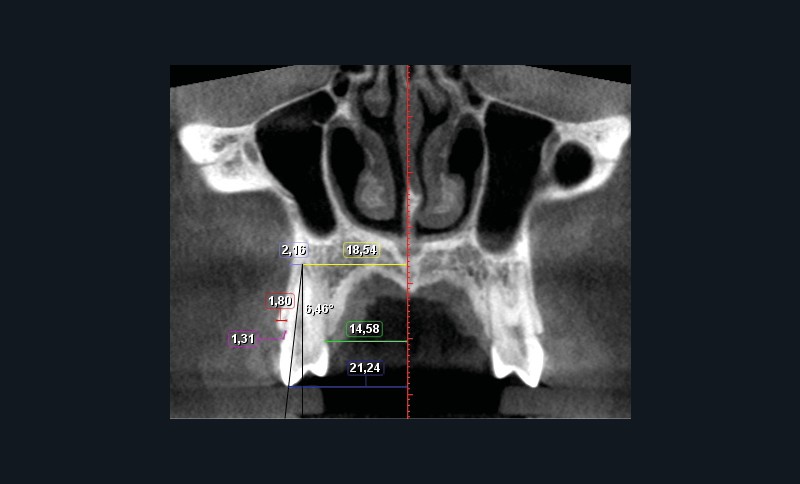

Sept mesures ont été réalisées pour quantifier le déplacement dentaire et les modifications alvéolaires (fig. 1 et 2). de chaque côté :

– largeur au niveau de l’apex ;

– largeur palatine mesurée au niveau du collet ;

– largeur au niveau de la cuspide vestibulaire ;

– quantité de version ;

– épaisseur de l’os alvéolaire à l’apex ;

– épaisseur de l’os alvéolaire coronaire mesurée à 2 mm apicalement à la crête ;

– distance jonction amélo-cémentaire-crête alvéolaire.